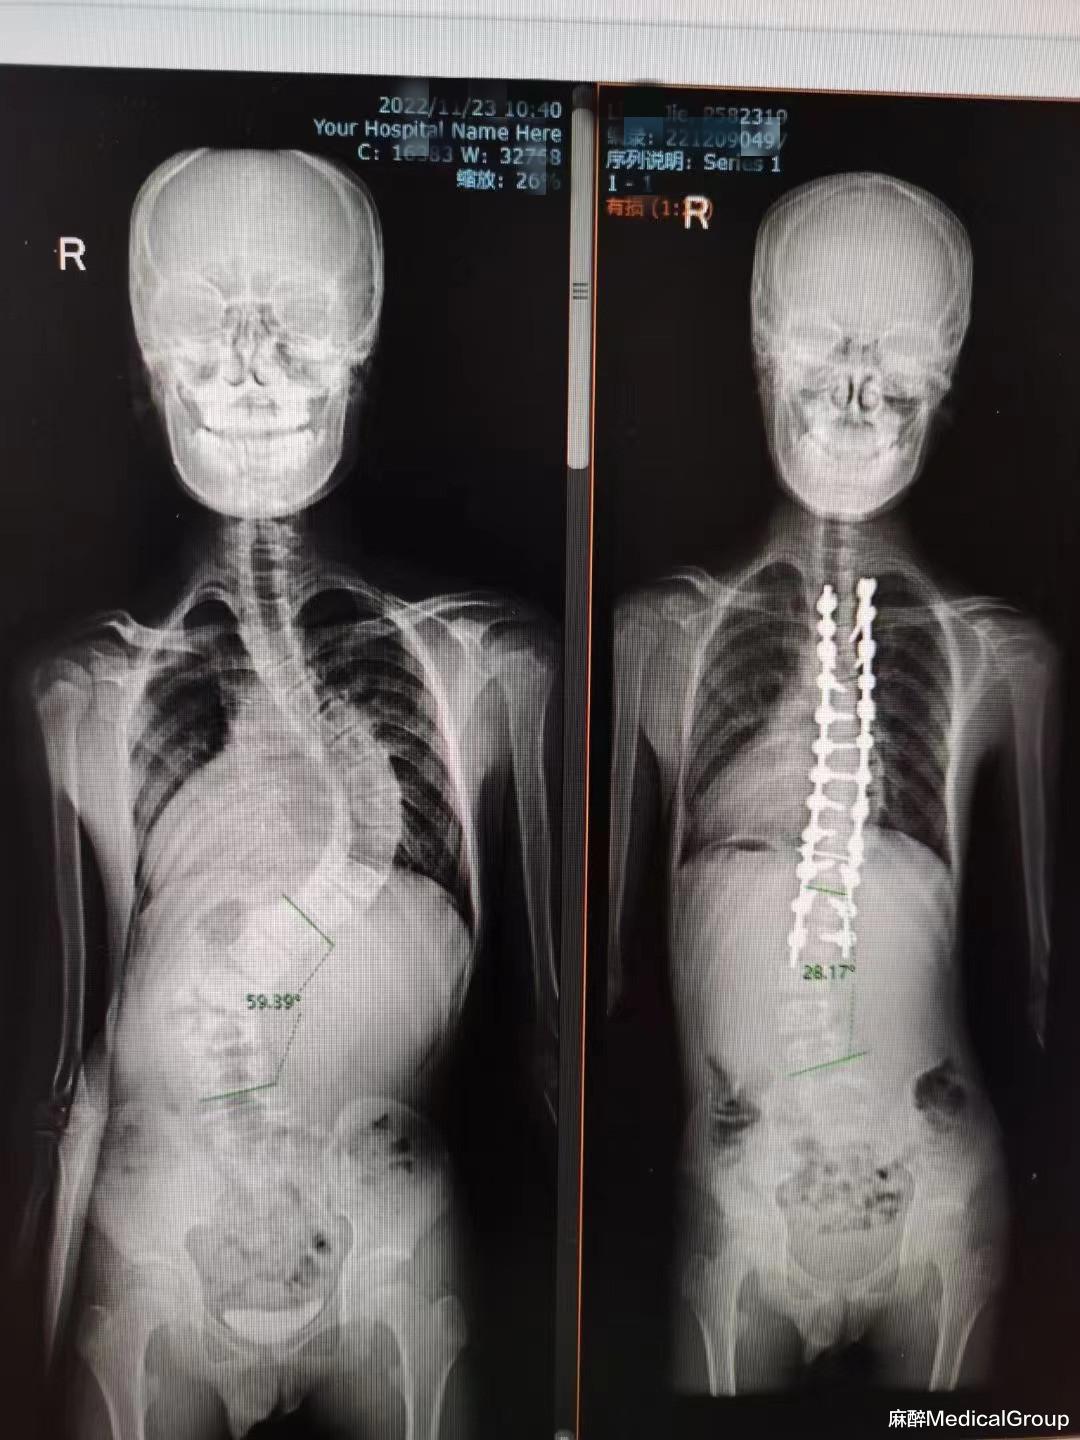

随着人群年龄增长 , 以及临床创新和技术的持续进步 , 麻醉医护人员将给予脊柱手术患者越来越多的照护 。 脊柱和脊髓的外科操作十分常见 , 可以因各种情况而实施 。 这类操作的复杂程度各异 , 范围从微创的单节段减压到高度复杂的多节段广泛性重建不等 。 退行性脊柱疾病和椎间盘突出的手术操作最常见于60岁以下患者 , 而60岁以上患者最常进行针对椎管狭窄的脊柱手术[1

重大脊柱手术可以导致显著出血 , 偶尔会导致大出血 。 失血严重程度因以下情况而增加:融合的椎体节段数量增加、年龄超过50岁、肥胖、肿瘤手术、俯卧位时腹腔内压力升高 , 以及实施经椎弓根截骨术 。 因此 , 对于围术期患者的血液保护显得十分重要 , 在我们麻醉过程中注意这些细节 , 尽量减少患者出血 , 提高围术期患者安全是我们麻醉医生义不容辞的责任!下面从以下几点简单叙述 , 希望对大家有些许的帮助 。